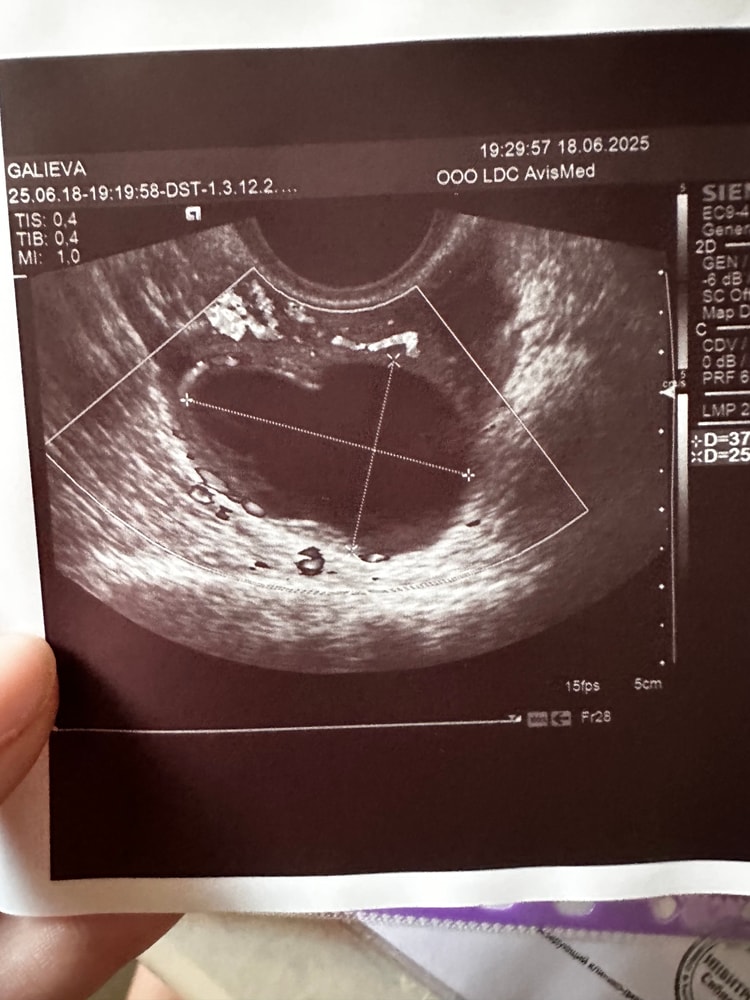

Хочу оставить на память свое странной формы желтое тело.

Не важно, какой формы, главное, что оно есть) удачи вам🤞